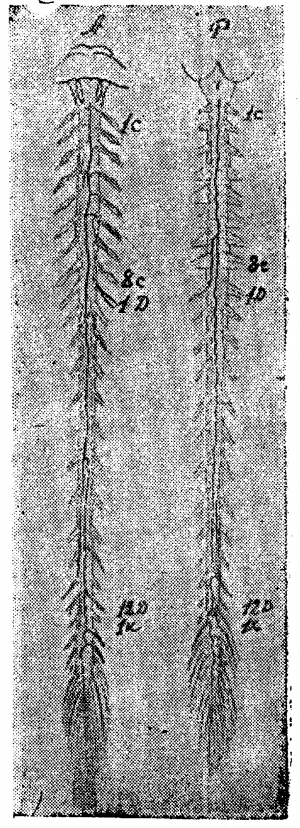

Мы уже неоднократно упоминали о работе Словохотова, исследовавшего развитие сосудов спинного мозга в эмбриональный период и показавшего, что закладка сосудов в эмбрионах проходит по эмбриональному типу, который ещё ясно выражен до 6-го лунного месяца. Во вторую половину утробной жизни происходит перестройка метамерного типа на стволовой (рис. 3 и 17).

По нашим исследованиям, у новорожденных строение вен спинного мозга уже приобретает все основные характерные черты, свойственные взрослому; мы можем совершенно определённо констатировать наличие продольных стволов, вены корешков выражены ясно, неравномерны по калибру и неравномерно распределяются.

В возрасте 4—5 месяцев внеутробной жизни, мы видели уже богато развитую поверхностную венозную сеть, но она ещё очень тонка, почти капиллярна. Передний средний венозный тракт вполне сформирован; боковые тракты намечаются на нашем препарате спереди, в грудном отделе спинного мозга. Вены спинно-мозговых корешков выражены хорошо, но ещё сохраняют эмбриональный тип в том отношении, что вены главных оттоков (корешков шейного и поясничного утолщения) ещё не так резко преобладают над другими корешковыми венами, как это бывает у взрослых.

Большая вена Адамкевича типично отходит от среднего переднего венозного тракта, очень хорошо развитого.

Задняя поверхность мозга на том же препарате представляет более пёструю картину: шейная часть задней поверхности покрыта тончайшей сетью вен, но продольное расположение сосудов по корешкам и задней расщелине уже намечается. Грудная часть препарата особенно интересна: с 8-м шейным корешком отходит (типично) вена спинно-мозгового нерва; сверху она соединена с венозными стволиками шейной сети, а книзу проходит в виде крайне извитого, часто пересекающего медиальную линию сосуда. Вены некоторых корешков (например, 2, 4 грудного) начинаются двумя корнями — верхним и нижним, так что намечается боковой тракт. Средний венозный тракт выравнивается в грудной области и змеится вдоль средней линии, причём на протяжении 6—7 грудных сегментов его сопровождает параллельный, уже хорошо сформированный стволик, спускающийся вдоль входа в мозг задних корешков. Оттоки в поясничной области развиты хорошо на 12-м грудном справа и на 1—2-м поясничных корешках слева.

В более старшем возрасте можно наблюдать уже вполне типичную для взрослых картину поверхностных вен спинного мозга.

Влияние возраста во второй половине жизни начинает сказываться, по нашим наблюдениям, лет с пятидесяти. На препаратах вен спинного мозга людей этого возраста можно видеть значительную извилистость вен и расширение их просвета. Чем выше возраст, тем яснее выражены эти изменения, расширяются не только продольные стволы, но также и оттоки, так что второстепенные оттоки по калибру начинают приближаться к главным. Это явление не следует смешивать с дисперсным строением оттоков, там сдвиг наблюдается в обратном направлении — главные оттоки остаются слабо выраженными и по калибру приближаются к второстепенным оттокам, число которых увеличено. Таким образом, при дисперсном типе наблюдается минус нивелировка, тогда как при старческих изменениях наблюдается плюс нивелировка.

Форма первая. Рис. 6, 7, 8 дают примеры первого типа.

На передней поверхности препарата, изображенного на рис. 6, можно отметить неравномерность калибра среднего ствола, склонность к образованию островков, но, в общем, тракт можно довольно легко проследить на всём его протяжении. На рис. 7 задержка редукции выражена больше: калибр переднего тракта очень мелок, тракт почти прерывается, отклоняясь несколько в сторону; боковые же тракты выражены относительно лучше. Гораздо больше выражена задержка редукции на препарате, изображённом на рис. 8. В нижней части шейного отдела и в грудном отделе средний тракт только отгадывается в системе продольных петель, с частыми боковыми оттоками (ср. верхнюю грудную область, особенно 3-й грудной сегмент, где средний тракт совершенно отходит в сторону, прерывается и оба его отрезка впадают отдельно в параллельные венозные стволики третьего грудного корешка). В области 12-го грудного—1-го поясничного сегмента тракт также отклоняется в сторону, образует островок и почти истощается. В грудной области тракт распадается на два слабых извилистых рукава, образующих длинный островок, а в области 8—11-го сегмента видны даже три параллельных стволика. Оттоки рассеяны, мелки, на одном корешке зачастую видны 2—3 венки. Вена Адамкевича выражена слабо (1 крестцовый корешок слева); боковые тракты едва намечаются прерывистой линией. Эту картину можно считать типичной задержкой редукции, наиболее выраженной для передней венозной сети в ряду изученных нами препаратов.

На рис. 9 видна неравномерность калибра переднего тракта, его извитость, рассеянность оттоков; на рис. 10 видны те же черты: тракт прерывается, извит, образует островки, во многих местах существуют довольно значительные параллельные стволы. Этот рисунок заслуживает внимания: на изображённом здесь препарате задержка редукции выражена и спереди и сзади, а вместе с тем венозные стволы поверхностной сети широки, налиты кровью и при невнимательном взгляде препарат легко отнести к магистральному типу, что было бы, конечно, ошибочно. Развитость стволов, набухлость вен в данном случае являются следствием возрастного изменения и нарушения венозного кровообращения у сердечнобольного (см. ниже гл. IV, болезни сердца).

Задняя поверхность препаратов, изображённых на рис. 6, 7, 8, 10, 11 представляет ещё более резкую картину задержки редукции первичной венозной сети. Так, на рис. 10, несмотря на резкую набухлость вен, в шейной и верхней грудной области почти не выражены продольные стволы: это еще ясней видно на рис. 11, где местами продольные стволы совсем не видны, местами же они только намечаются. Изображённый на рисунке препарат представляет большой интерес с патологической точки зрения и к нему мы вернёмся в гл. IV.

Очень типична картина задержки редукции первичной венозной сети задней поверхности, видная на рис. 7. Мы отмечаем резкую неравномерность калибра и плохое развитие среднего тракта, отклонение от средней линии, перерыв на уровне 7-го — 11-го грудного сегмента, плохую выраженность продольных стволов, местами трудно выделяемых из венозной сети, рассеянность оттоков. Аналогичная картина видна и на рис. 8.

Вторая форма. Магистральный тип поверхностных вен спинного мозга характеризуется двумя основными чертами: хорошей выраженностью среднего тракта и хорошей централизацией оттоков. Боковые продольные тракты обычно только намечаются и, повидимому, вообще редуцируются (рис. 12, 13, 14).

На рис. 12 довольно хорошо выражен магистральный тип вен передней поверхности, строение же вен задней поверхности является переходным. Лучше магистральный тип выражен на обеих поверхностях препарата, изображённого на рис. 13, где почти не видны боковые тракты, а средние тракты представляются хорошо развитыми, относительно равномерными по калибру, оттоки хорошо централизованы. На рис. 14, 15, 16, 17 и 18 можно видеть различные переходные вариации.

Сравнительно-анатомические данные убеждают нас, что продольные сосуды спинного мозга развились постепенно в длинном филогенетическом ряду и не с одинаковой интенсивностью для разных трактов и разных участков этих трактов. Развитие трактов шло путём укрепления анастомозов между отдельными метамерами спинного мозга, причём процесс продвигался значительно быстрее в головных метамерах и заметно запаздывал в хвостовых. Это ясно сказывается на картине поверхностных вен не только зародышей, но и взрослого человека. Сосуды вещества мозга ещё и у человека сохранили характер цепи анастомозов. Анастомозная цепь поверхностных сосудов спинного мозга ещё вполне выражена у птиц, и только у млекопитающих она заменяется продольными трактами. Итак, первый этап образования сосудистых трактов поверхности спинного мозга характеризуется движением от метамерно-поперечного распределения сосудов к продольному. Дальнейшее движение — редукция продольных стволов и количества оттоков. Процесс этот ещё не завершён у человека, особенно на задней поверхности спинного мозга. Боковые венозные стволы задней поверхности образуются, по данным Словохотова, к шестому лунному месяцу утробной жизни, а к седьмому они значительно редуцируются в пользу среднего тракта, расположенного в филогенетически наиболее молодом участке органа. Белое вещество спинного мозга орошается приблизительно вдвое менее интенсивно, чем серое, этим и объясняется слабое развитие боковых продольных трактов, а также их индивидуальная нестойкость, изменчивость. Задние боковые тракты развиты сильнее передних, так как первые получают кровь из более обширной области боковых столбов, отчасти задних столбов и задних рогов (через анастомозы вен серого и белого вещества мозга), тогда как передние тракты получают кровь только из передних столбов и отчасти из передних рогов. Передний венозный тракт филогенетически надо считать основным, так как он выносит кровь из древнейших отделов органа; большая часть крови поступает в него из серого вещества. Этим объясняется большая индивидуальная устойчивость тракта, малая его изменчивость по сравнению с задним. Отток крови с передней поверхности гораздо лучше централизован, нежели с задней: количество развитых венозных стволиков передних корешков приблизительно вдвое меньше, чем задних, но калибр их крупнее. Редукция первичной венозной сети всегда больше выражена спереди, чем сзади. В зависимости от степени редукции поверхностных вен спинного мозга, можно наметить два крайних типа их изменчивости: 1 — метамерно-дисперсный, 2 — продольно-магистральный. Их подробная характеристика дана выше.